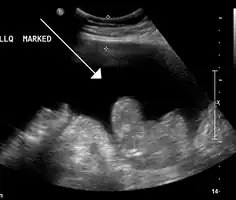

Ultrasound investigation is often performed prior to attempts to remove fluid from the abdomen. This may reveal the size and shape of the abdominal organs, and Doppler studies may show the direction of flow in the portal vein, as well as detecting Budd-Chiari syndrome (thrombosis of the hepatic vein) and portal vein thrombosis. Additionally, the sonographer can make an estimation of the amount of ascitic fluid, and difficult-to-drain ascites may be drained under ultrasound guidance. An abdominal CT scan is a more accurate alternate to reveal abdominal organ structure and morphology.

• Grade 1: mild, only visible on ultrasound and CT